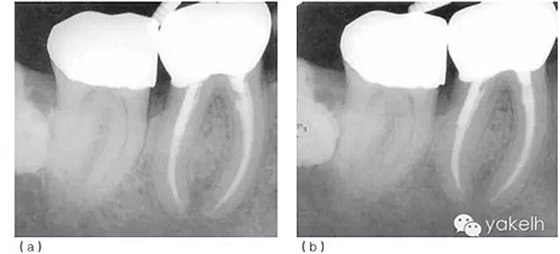

圖5.1.2(a)46根管再治療前X線片?,F(xiàn)有修復(fù)體、核及兩個不銹鋼樁均已安全拆除,患牙用不銹鋼帶環(huán)和Ketac-SilverTM臨時修復(fù),這為后續(xù)治療提供了無微滲漏且穩(wěn)定的局部環(huán)境。(b)46根管再治療后X線片。與圖5.1.1相比,根管預(yù)備和充填更接近理想的工作長度,致密度更高。

術(shù)后觀察愈合情況。最后制作新的樁冠。術(shù)后2年、6年復(fù)查,X線片顯示根尖周病損逐漸恢復(fù)(圖5.1.3)。

圖 5.1.3(a)根管再治療后2年復(fù)查,X線片顯示46根尖周骨重建、遠(yuǎn)中根管內(nèi)金屬樁、金合金冠修復(fù)。(b)根管再治療后6年復(fù)查,X線片顯示46根尖周完全恢復(fù)。